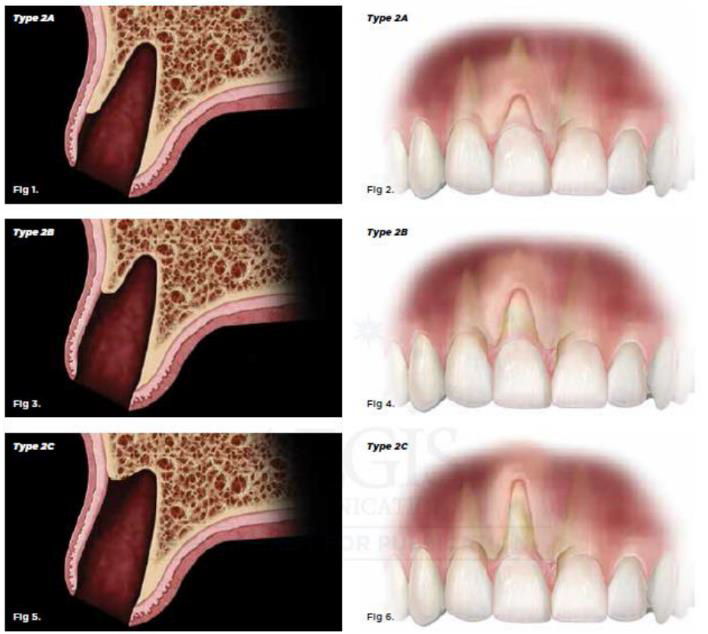

Elian

- Type1:軟組織與硬組織皆好

- Type2:軟組織完整但硬組織有垂直方向的缺損(不管缺損多少)

- Type2A:唇側缺損(或說dehiscence)高度在上1/3(靠牙冠)

- Type2B:唇側缺損(或說dehiscence)高度在中1/3

- Type2C:唇側缺損(或說dehiscence)高度在下1/3(靠根尖)

- Type3:軟組織與硬組織皆有缺損